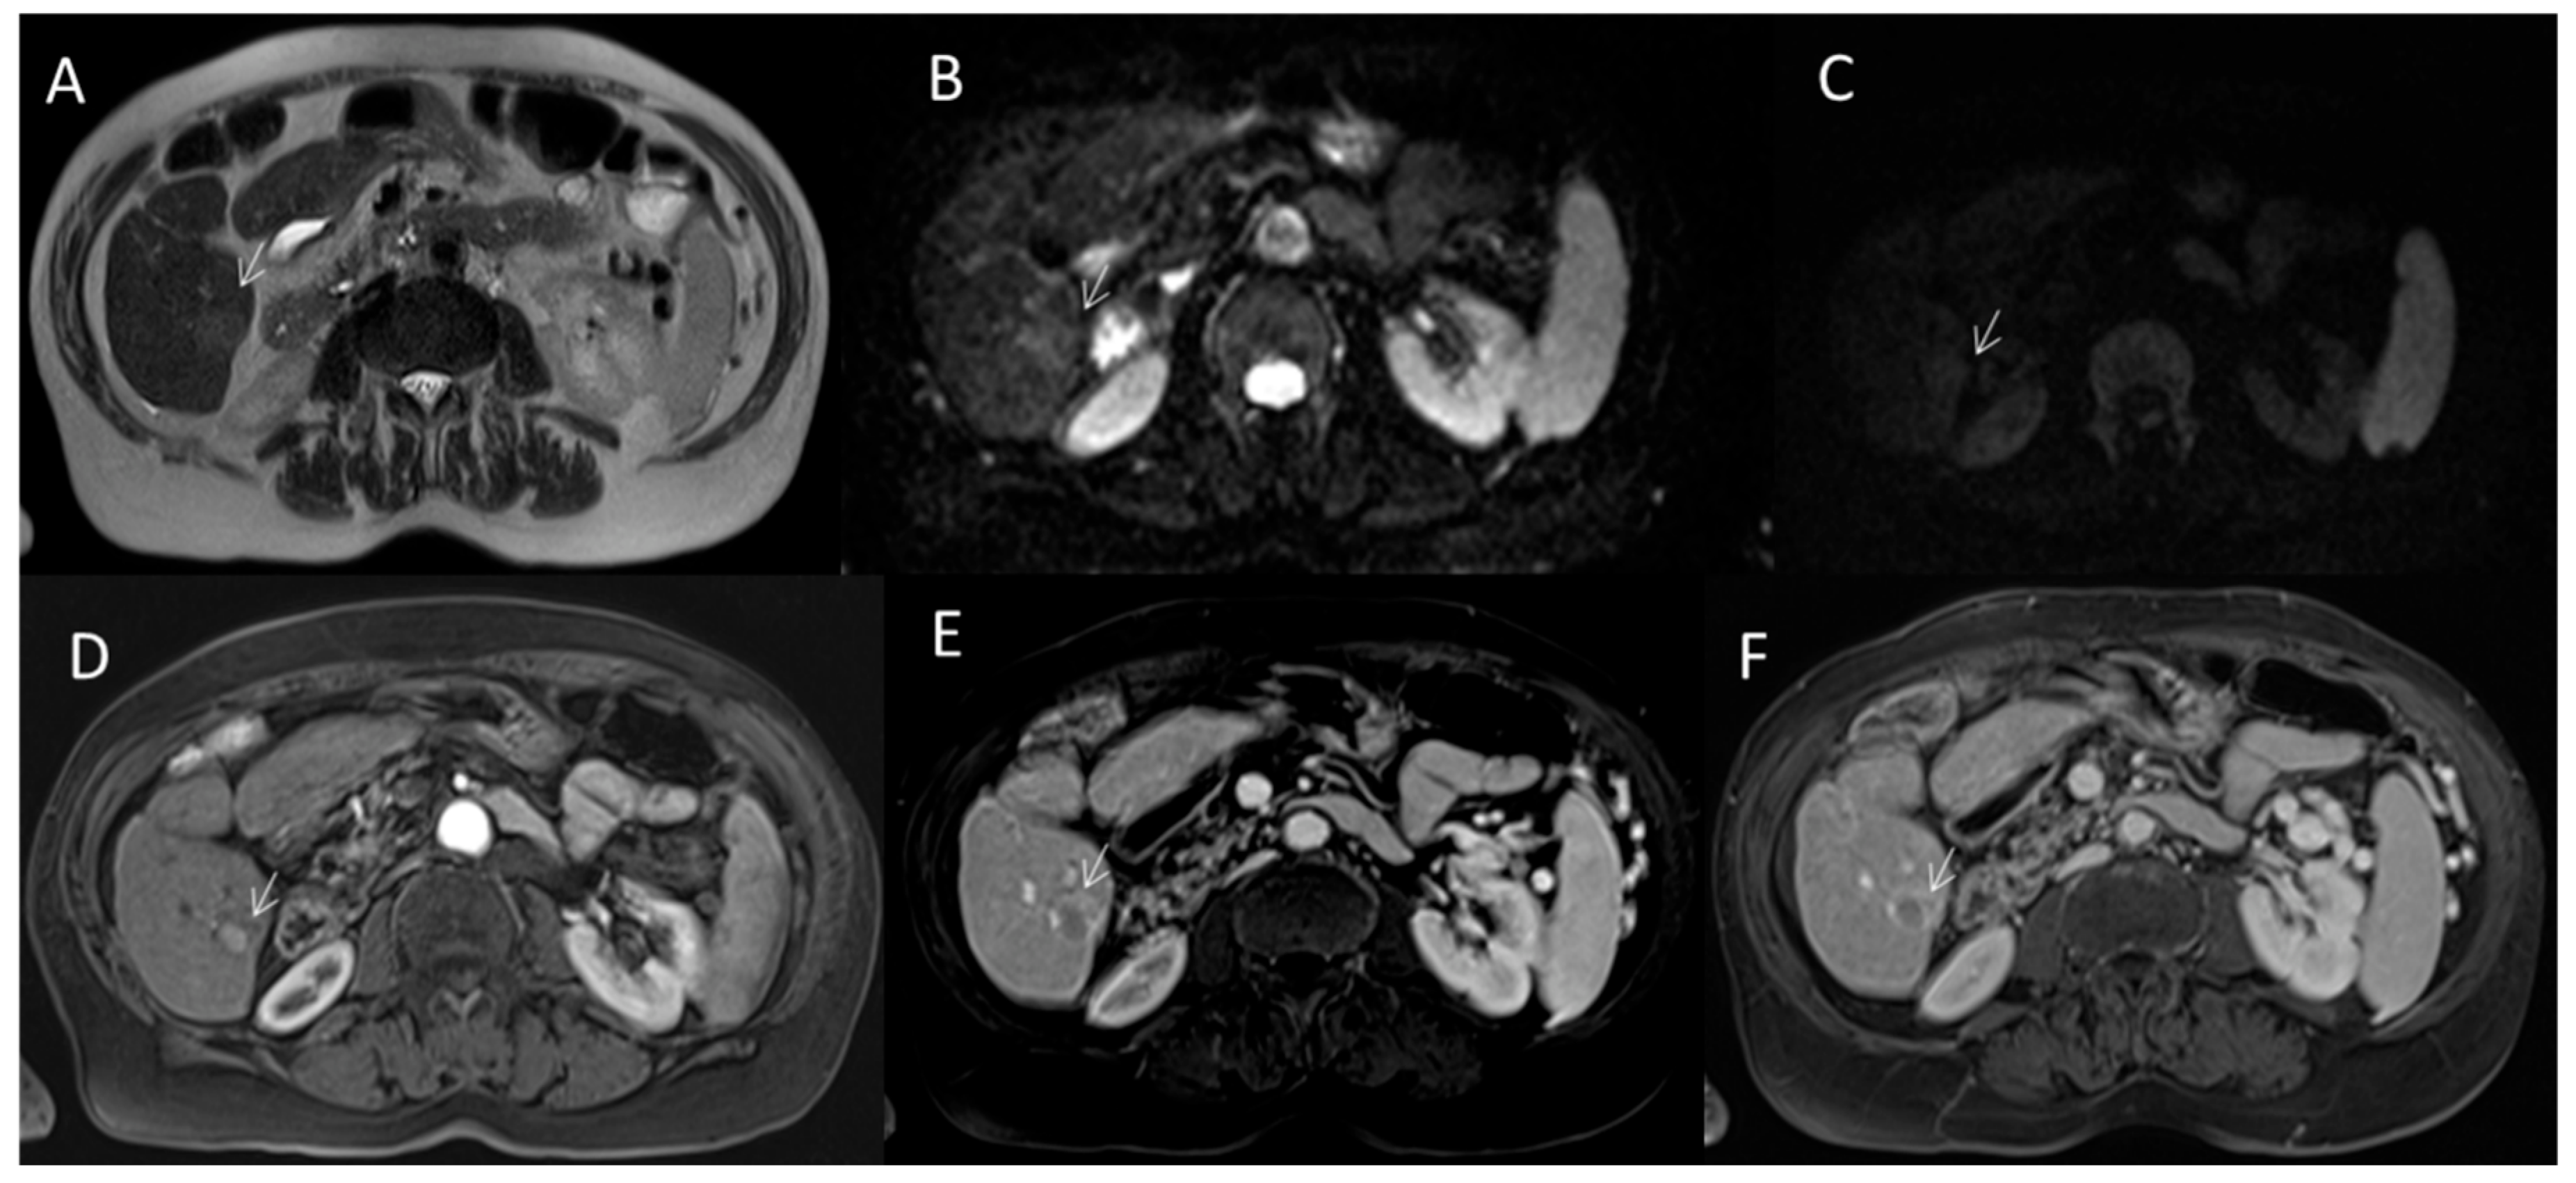

2.2.5. LR-M Category

2.3. CEUS-LI-RADS

2.3.2. CEUS-LI-RADS Categories